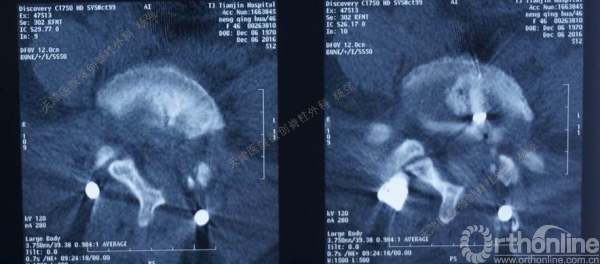

腰5椎体前滑脱I-II°,峡部裂,动力位显示腰5-骶1节段明显失稳

CT、MRI示:腰5椎体前滑脱,腰5/骶1水平间盘突出,腰5双侧椎弓峡部裂